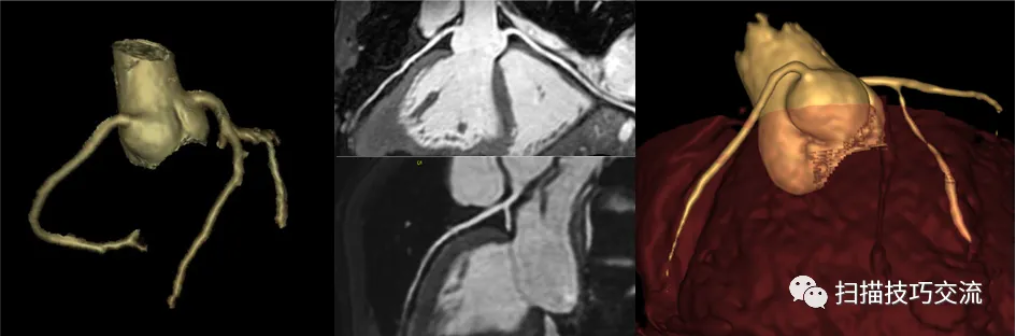

3,成像效果

图像来自浙江大学第一附属医院,非常感谢汪启东教授商德胜教授提供图像。